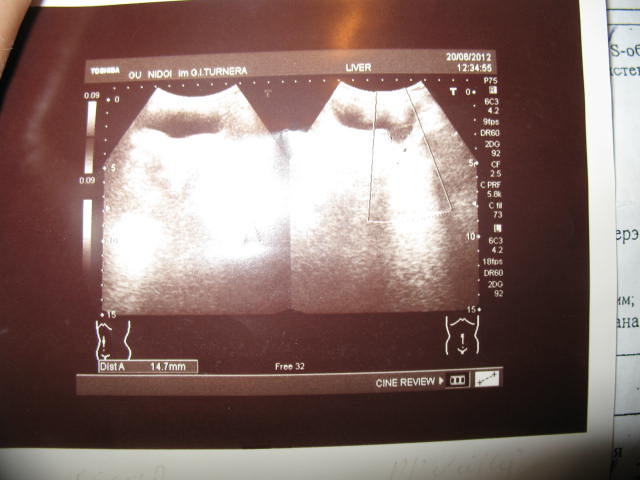

Что касается УЗИ мочевой системы,в 2012 г. после удаления металлоконструкций из бедра и таза было сделано УЗИ. Предполагаемый диагноз- дивертикул мочевого пузыря (фото +описание прилагаю).УЗИ выполнено в Ин-те им.Турнера, Санкт-Петербург. В дальнейшем регулярно проводили УЗИ в Приднестровье.Один из специалистов постоянно выставляет двустороннюю пиелоэктазию.Другой же патологии не видит (его свежий результат прилагаю)...Впрочем,в своё время на УЗИ он не смог диагностировать дочери врожденный порок сердца...Потому Ваш посыл о КВАЛИФИЦИРОВАННОМ обследовании,надеюсь,будет реализован.Есть возможность отправиться в Москву или Казань-каков Ваш совет? Есть ещё один настораживающий фактор: после перенесенного в возрасте трех лет острого гломерулонефрита в моче ребёнка регулярно выявляются единичные эритроциты (до 5 в поле зрения). Помимо этого, в возрасте двух недель жизни по ошибке был отключен кувез ,в котором находился мой ребёнок (шрам в памяти:зав.отделением вместо "извините" с улыбкой произнесла:"Это для нас эксклюзив!"). Температура внутри кувеза вместо необходимой +33-34 опустилась до +15. В результате переохлаждения- пневмония+ОСТРЫЙ ПИЕЛОНЕФРИТ.Антибиотики-в течение всего первого месяца жизни.Отечность (выраженные мешки под глазами) сохранялась в течение нескольких месяцев...Но тогда мы не думали о почках.Эйфория оттого,что ребёнок наконец=то дома ,искажала восприятие реальности.Ещё не наступил кризис доверия докторам. И мы верили в то,что раз выписали,значит здоров! ...В 5 месяцев жизни невролог назначил триапмур ежедневно в течение месяца (лето-+40 в тени,единственное поступление жидкости-грудное молоко;воду,к сожалению,не пили...Ещё одно испытание для почек. ...Постепенно рассеивались иллюзии . И пришло осознание того,что,к сожалению, отечественная система здравоохранения КАК СИСТЕМА не работает, а ВЫЖИВАЕТ благодаря отдельным энтузиастам...Наверное,благодаря таким,как ВЫ,Алексей Денисов;как ВЫ, Михаил Юдович...

Tatiana-Anna, По описанию УЗИ почки выглядят совершенно не изменёнными + нормальная величина креатинина сыворотки позволяет исключить почечную недостаточность. Я думаю, у Вас нет хронической болезни почек. Сложнее задним числом дать оценку имевшихся в прошлом проявлений гломерулонефрита. Острый гломерулонефрит болезнь одноразовая - судя по УЗИ - он существенных последствий не оставил, небольшое количество эритроцитов в моче после этого может оставаться на годы и я бы не волновался по этому поводу. Остаётся не вполне ясным, что с мочевым пузырём? Дивертикул? Уретероцеле? Но этот вопрос можно выяснить только очно у хорошего детского уролога.